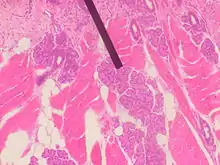

Von Ebner's glands, also called Ebner's glands or gustatory glands, are exocrine glands found in the mouth. More specifically, they are serous salivary glands which reside adjacent to the moats surrounding the circumvallate and foliate papillae just anterior to the posterior third of the tongue, anterior to the terminal sulcus.

Von Ebner's glands secrete lingual lipase,[1] beginning the process of lipid hydrolysis in the mouth. These glands empty their serous secretion into the base of the moats around the foliate and circumvallate papillae. This secretion presumably flushes material from the mouth to enable the taste buds to respond rapidly to changing stimuli.